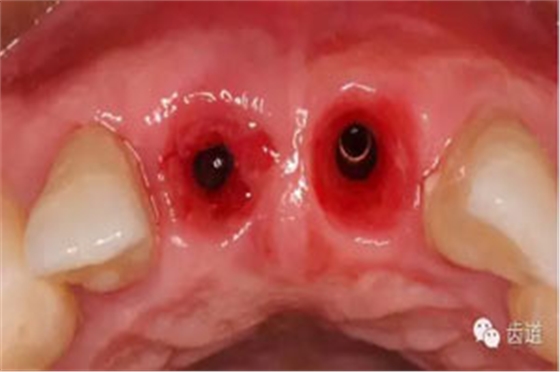

半年后復(fù)診

Cbct影像

袖口形態(tài)